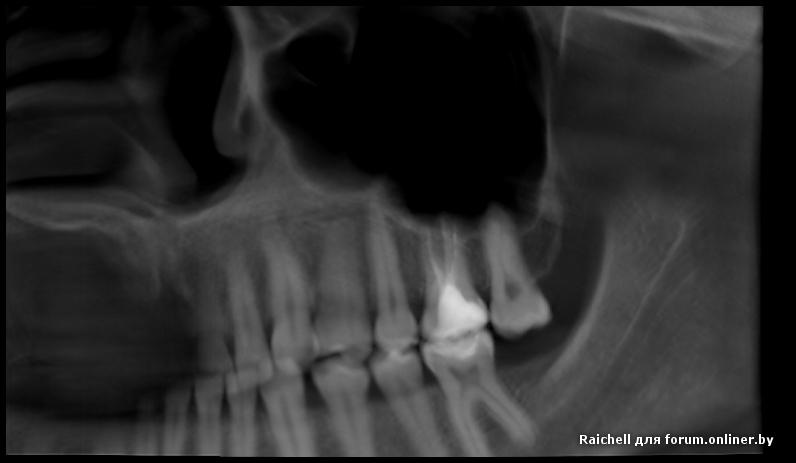

Во всех депульпированых зубах есть проблемы, плюс в пазухе слева от 25 зуба есть нюанс

inycik:Во всех депульпированых зубах есть проблемы, плюс в пазухе слева от 25 зуба есть нюанс

16,15 на удаление, потом синус и имплантация

Все зубы перелечила. это кт до лечения. Сейчас под временными коронками. Предлагают имплантацию 1.5,2.5 и 4.5 (убрать мост, т.к. 4.6 сильно разрушен). 1.5 удалить и сразу же имплант, но про наращивание не говорили.

А скажите, что в пазухе? Это как-то повлияет на имплантацию